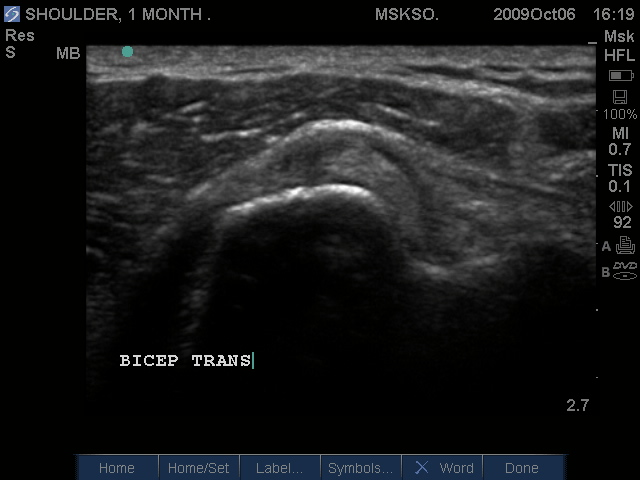

Subluxing Bicep tendon over lesser tuberosity

Subluxing Bicep tendon over proximal lesser tuberosity

Splitting Bicep tendon over lesser tuberosity